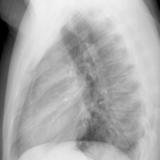

Case 8b Thymoma Lat